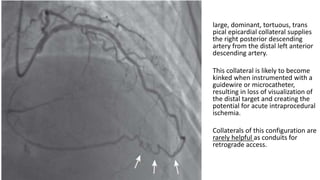

large, dominant, tortuous, trans

pical epicardial collateral supplies

the right posterior descending

artery from the distal left anterior

descending artery.

This collateral is likely to become

kinked when instrumented with a

guidewire or microcatheter,

resulting in loss of visualization of

the distal target and creating the

potential for acute intraprocedural

ischemia.

Collaterals of this configuration are

rarely helpful as conduits for

retrograde access.